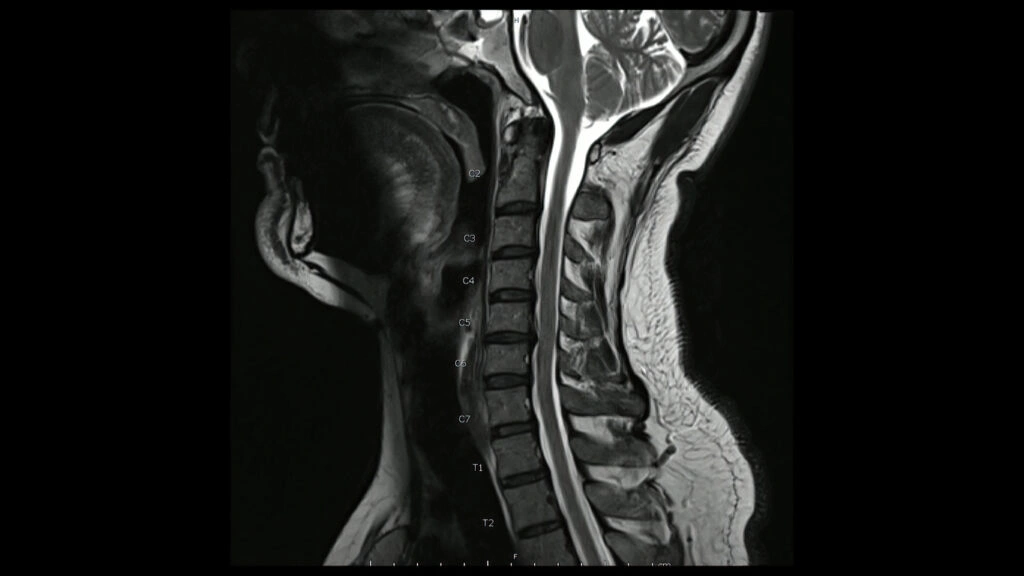

Bulging C5-C6 Disc Symptoms: Anchorage Chiropractor Explains: It’s More Than Just Neck Pain

A bulging disc in the C5-C6 area of your neck can disrupt your daily life in more ways than one. It can turn simple tasks like turning your head or reaching for an item into a painful ordeal. For many, the cycle of pain may seem never-ending. But there may be a light at the […]